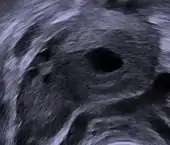

Order of changes in ovary Human ovary with fully developed corpus luteum

Human ovary with fully developed corpus luteum Luteinized follicular cyst. H&E stain.